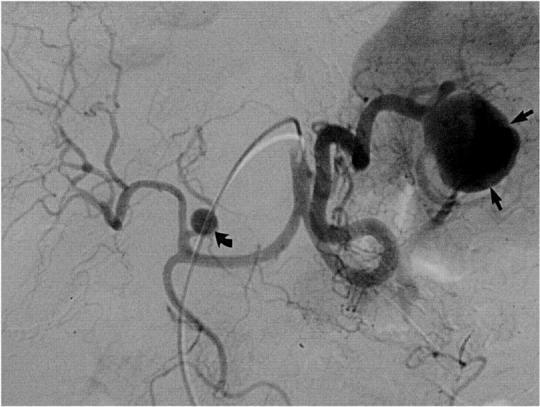

Артеріографія селезінкової артерії

- проводиться для діагностики цирозу печінки і деяких захворювань крові, а також аневризм селезінкової артерії.